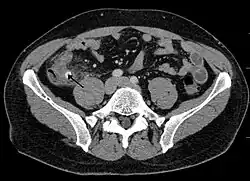

CT scan showing acute appendicitis

Diagnosis is based on a medical history (symptoms) and physical examination, which can be supported by an elevation of neutrophilic white blood cells and imaging studies if needed. Histories fall into two categories, typical and atypical.

A CT scan demonstrating acute appendicitis (note the appendix has a diameter of 17.1 mm and there is surrounding fat stranding)

Where it is readily available, computed tomography (CT) has become frequently used, especially in people whose diagnosis is not obvious on history and physical examination. Concerns about radiation tend to limit use of CT in pregnant women and children, especially with the increasingly widespread usage of MRI.[49][50]

The accurate diagnosis of appendicitis is multi-tiered, with the size of the appendix having the strongest positive predictive value, while indirect features can either increase or decrease sensitivity and specificity. A size of over 6 mm is both 95% sensitive and specific for appendicitis.[51]

However, because the appendix can be filled with fecal material, causing intraluminal distention, this criterion has shown limited utility in more recent meta-analyses.[52] This is as opposed to ultrasound, in which the wall of the appendix can be more easily distinguished from intraluminal feces. In such scenarios, ancillary features such as increased wall enhancement as compared to adjacent bowel and inflammation of the surrounding fat, or fat stranding, can be supportive of the diagnosis. However, their absence does not preclude it. In severe cases with perforation, an adjacent phlegmon or abscess can be seen. Dense fluid layering in the pelvis can also result, related to either pus or enteric spillage. When patients are thin or younger, the relative absence of fat can make the appendix and surrounding fat stranding difficult to see.[52]